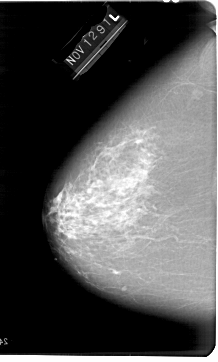

A_1648_1.LEFT_CC

LEFT_CC LINES 6871 PIXELS_PER_LINE 4141 BITS_PER_PIXEL 12 RESOLUTION 43.5 NON_OVERLAY